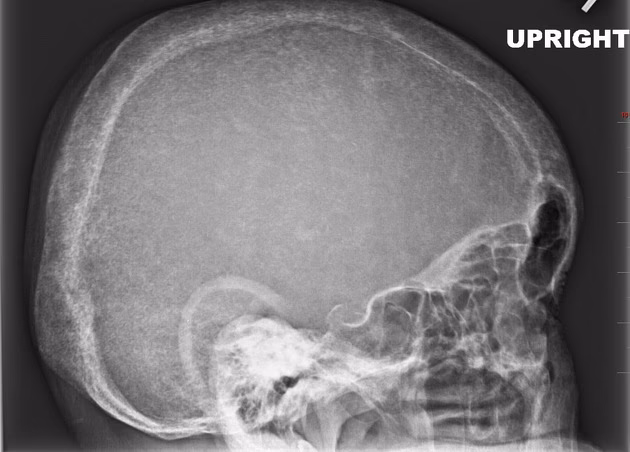

Den sjældneste manifestation, som forekommer hos mindre end 1% af patienterne, er thyroid akropaki. Dette er en tilstand, der påvirker knoglerne i hænder og fødder. Den er kendetegnet ved:

• Clubbing: Fortykkelse og opsvulmning af de yderste led af fingre og tæer, hvilket får neglene til at bue nedad.

• Hævelse: Bløddelshævelse i hænder og fødder.

• Periosteal knoglenydannelse: Røntgenbilleder kan vise ny knogledannelse langs de eksisterende knogler i hænder og fødder.

Akropaki ses næsten udelukkende hos patienter, der også har svær oftalmopati og dermopati, og er et tegn på en meget aktiv autoimmun proces.